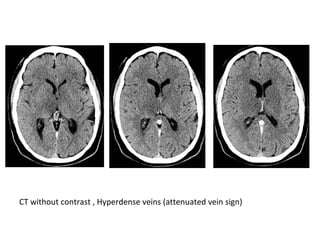

*CT :

-Acute thrombus is hyperdense on precontrast CT

and expands the occluded sinus / vein (Dense

clot sign)

- Cord sign : is defined as a homogeneous ,

hyperattenuated appearance of thrombosed

venous sinuses , the hyperattenuated

appearance of the affected veins often being

named (the attenuated vein sign)

CT without contrast , Hyperdense veins (attenuated vein sign)

CT without contrast , Hyperdense internal cerebral veins

(attenuated vein sign)